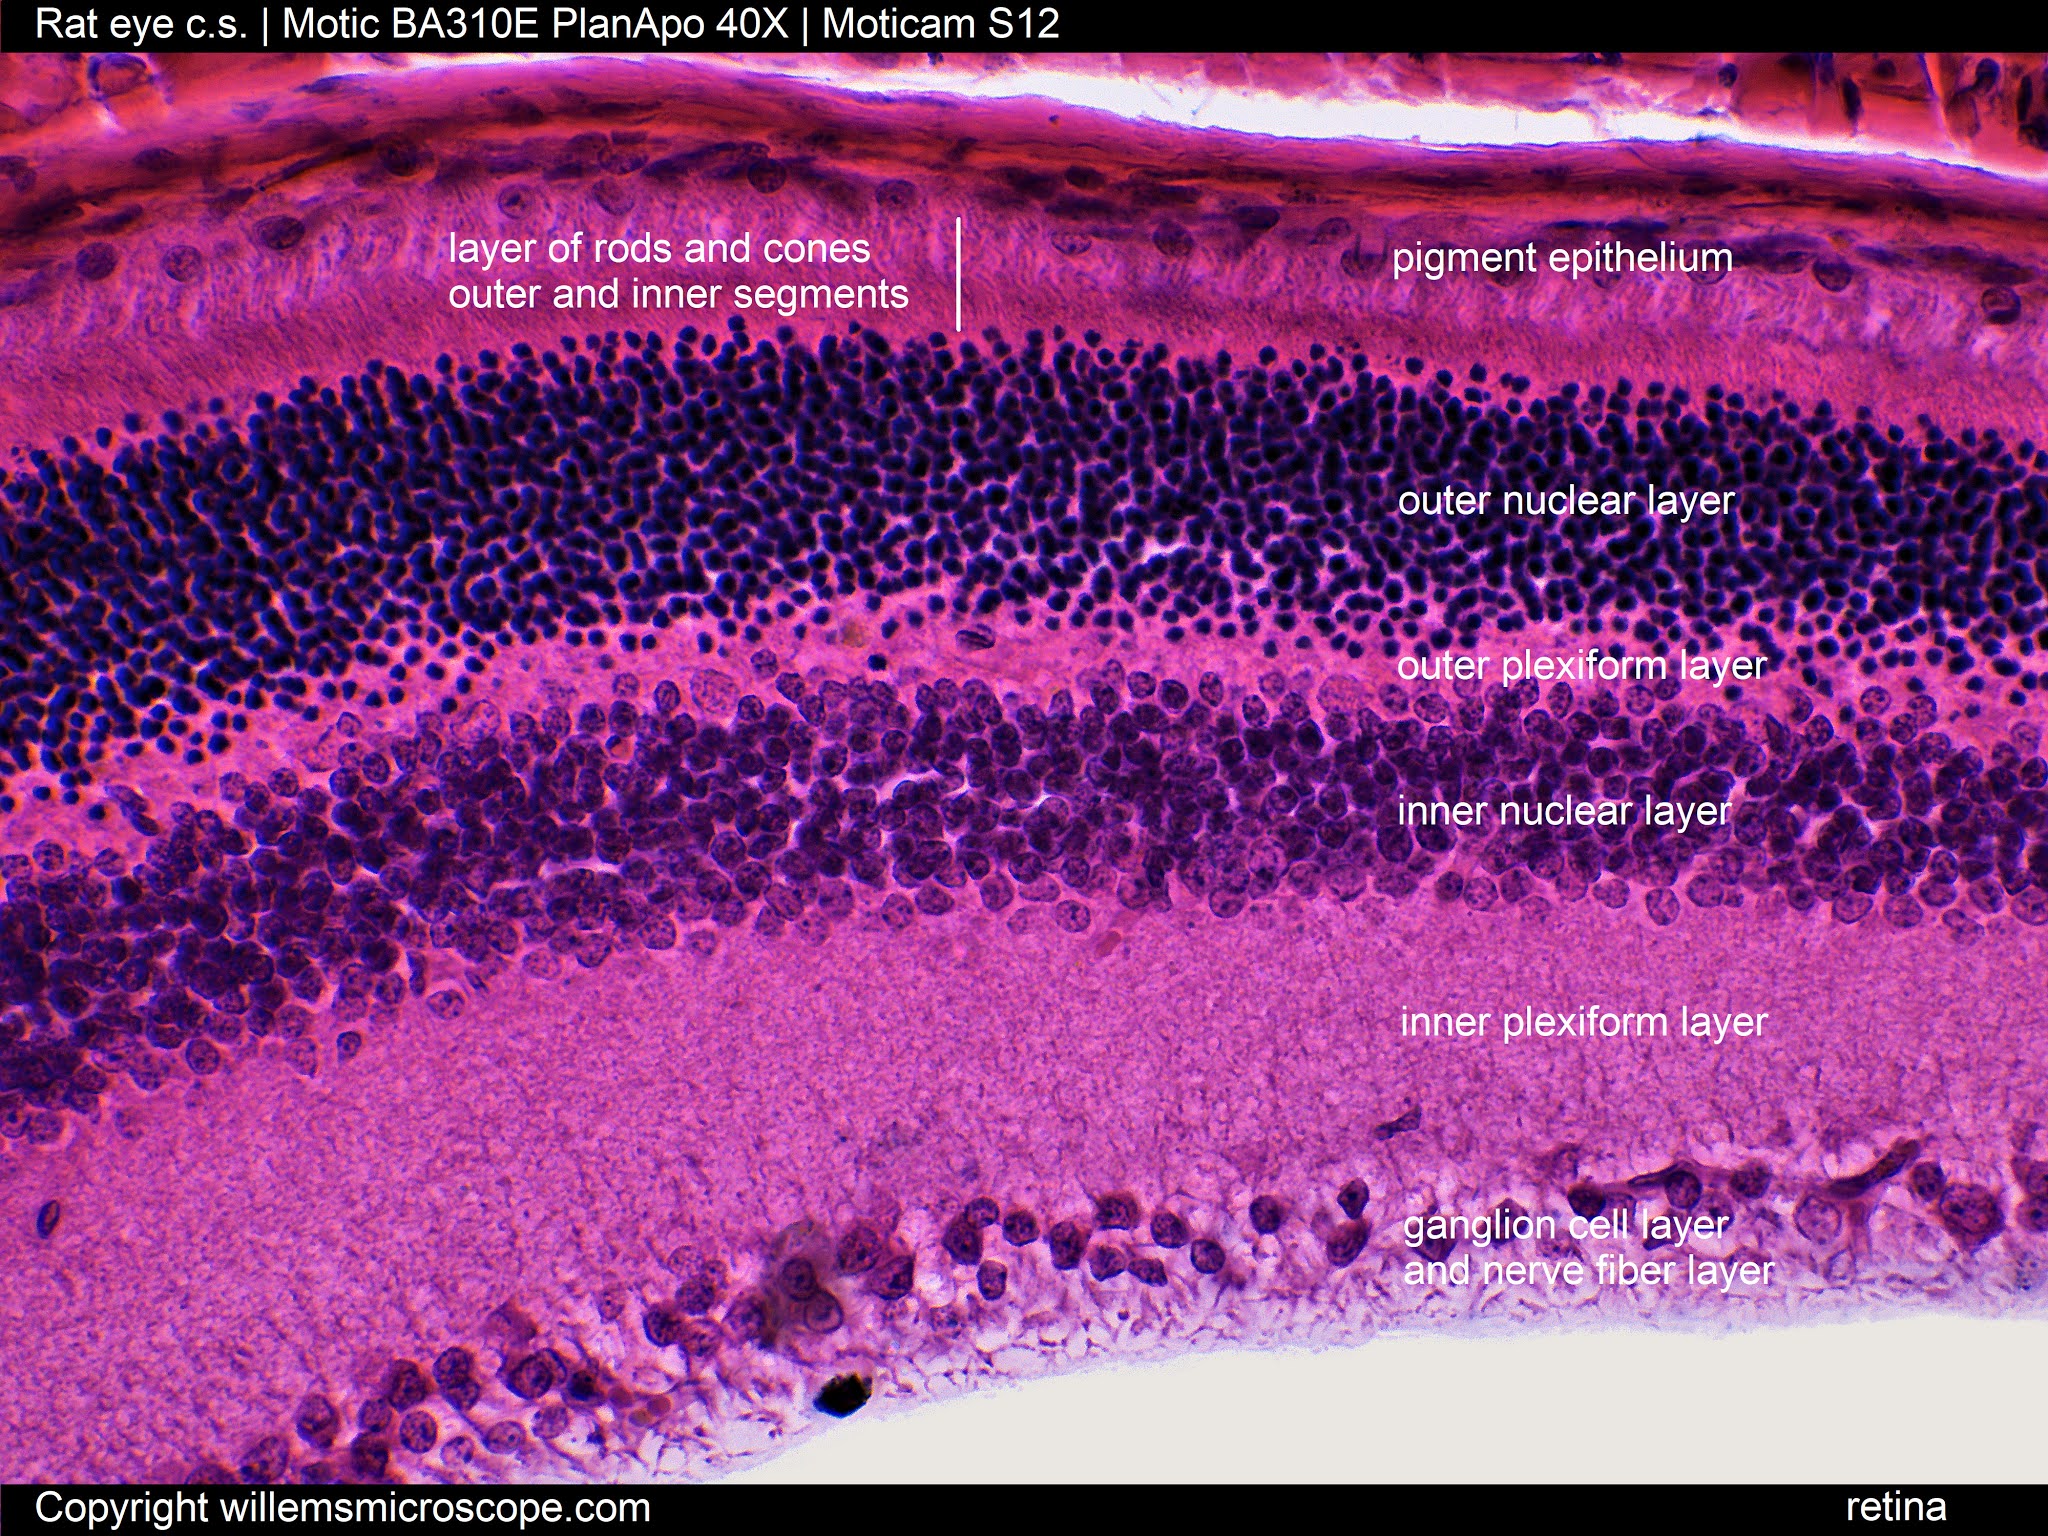

The photos show various parts of the rat's eye. There are many similarities between the eyes of the rat and those of humans, but also some striking differences. A few of these are mentioned here.

Humans have two types of photoreceptors: one type that senses light and dark, called rods, and one that senses colours, called cones. Humans have three types of cones: green, blue, and red. Rats have rods and cones as well, but only two types of cones: green and blue. Therefore, rats are unable to see reds. In addition, the rat's blue cones are sensitive to shorter wavelengths than our blue cones, which means that rats can see into the ultraviolet.

The rat retina has a very ‘coarse’ neural grain. Each neural cell in the rat retina is responsive to a much larger number of photoreceptors than those of the human retina, which increases sensitivity at the expense of acuity.